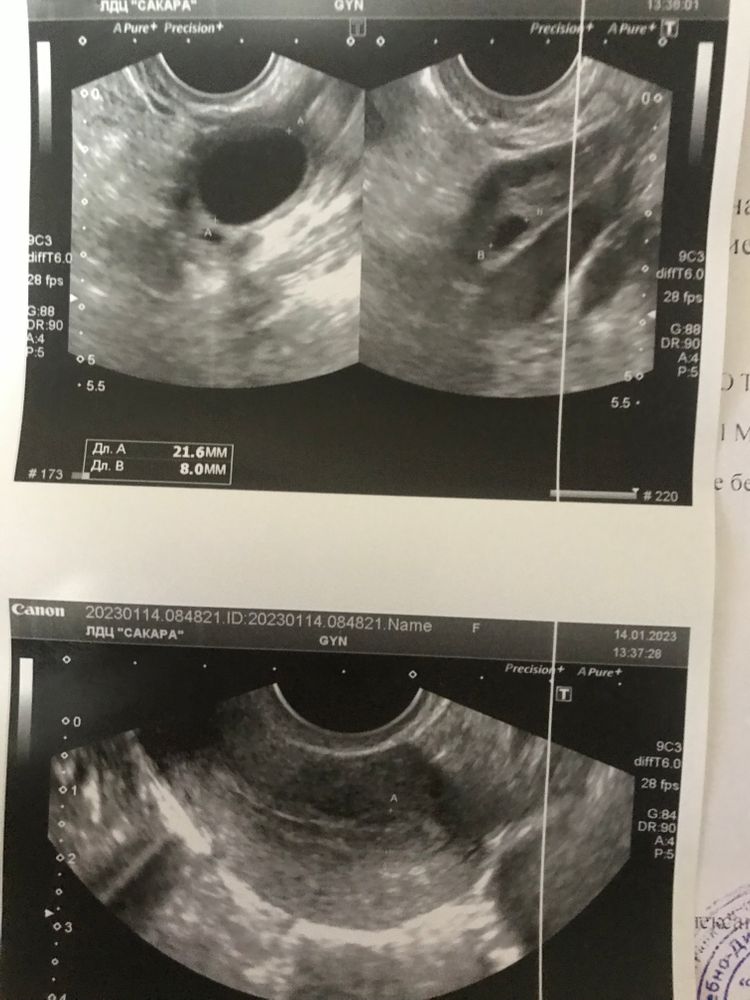

Здравствуйте, по узи должна быть скоро овуляция, но это первый цикл после чистки зб и хгч еще не спал. Сегодня 17дц дф 21,6мм. Может быть овуляция при хгч примерно 150 по значению? (Интерес не в целях планирования, а в целях восстановления цикла).

Судя по УЗИ, цикл почти восстановился. Почему "почти", т.к. эндометирй 6 мм - маловат для овуляции. Но фолликул почти предельный для овуляции. Но в матке недостаточный эндометрий для нидации плодного яйца. С беременностью придется еще 5 месяцев подождать За это время рекомендую пройти обследование, выявить причину остановки в развитии беременности, раз гистологического результата нет.